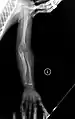

OI Type V in an adult

Having the same clinical features as Type IV, it is distinguished histologically by "mesh-like" bone appearance. Further characterized by the "V triad" consisting of (a) radio-opaque band adjacent to growth plates, (b) hypertrophic calluses at fracture sites, and (c) calcification of the radio-ulnar interosseous membrane.[24]

OI Type V leads to calcification of the membrane between the two forearm bones, making it difficult to turn the wrist. Another symptom is abnormally large amounts of repair tissue (hyperplasic callus) at the site of fractures. Other features of this condition include radial head dislocation, long bone bowing, and mixed hearing loss.